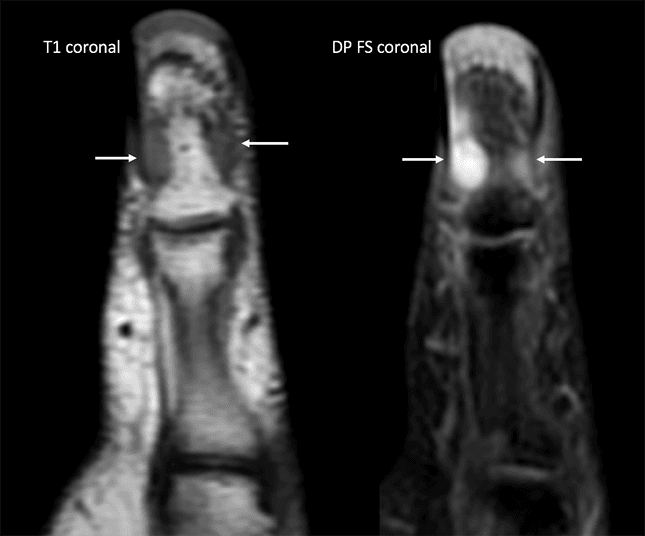

Ressonância magnética (RM) do primeiro quirodáctilo em plano coronal, sequências ponderadas em T1 e densidade protônica com saturação de gordura.

Observa-se imagem nodular sólida com sinal intermediário em T1 e alto sinal em densidade protônica com saturação de gordura, localizada junto ao leito ungueal da falange proximal do I dedo com contornos regulares e limites bem definidos.